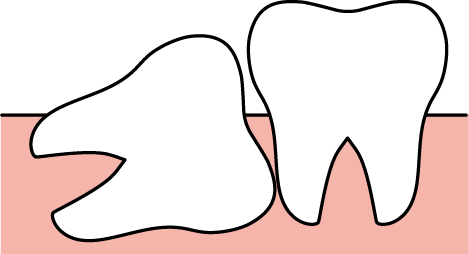

まっすぐ生えている場合は簡単な抜歯で済みますが、横向きや骨の中に埋まっている「埋伏歯」の場合は外科的処置が必要となります。

骨や歯ぐきの中に埋まっている「埋伏歯」は、腫れ・膿み・口臭の原因になることもあります。